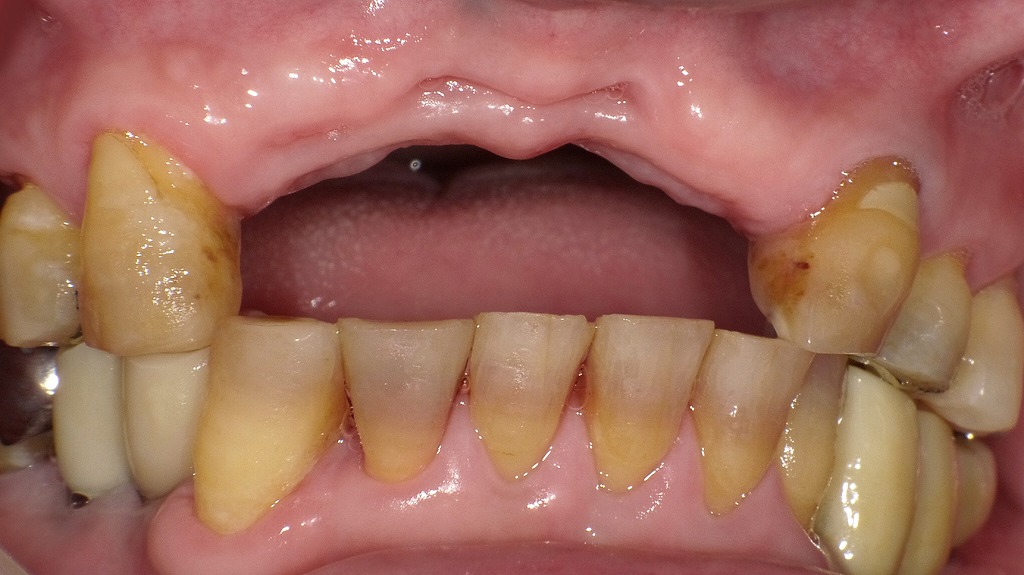

根管治療が失敗した症例

このデンタルX線写真は、上顎右側の前歯部(2番・3番)に根尖病巣(こんせんびょうそう)が確認できる症例です。以下に詳細を説明します。

🦷 所見の概要

- 対象歯:上顎右側2番(側切歯)および3番(犬歯)

- 根尖部の透過像:両歯の根尖部に黒っぽい(X線透過性の高い)領域があり、これは骨が溶けている=炎症による骨吸収を示しています。

- 診断名:根尖性歯周炎(根尖病巣)

🔍 考えられる原因

- 根管治療の失敗(再感染)

根管内に残存細菌がいる、または根尖まで十分に清掃・封鎖できていないために炎症が再発した可能性が高いです。 - 根尖封鎖不全

ガッタパーチャによる根管充填が根尖までしっかり届いておらず、感染経路が残っている状態が見られます。 - メタルコアによる再治療困難

金属製のポスト(メタルコア)が挿入されており、再根管治療を行う際に除去が難しいことがあります。

⚡ 臨床症状

- 自発痛(何もしなくてもズキズキ痛む)

- 咬合痛(噛んだ時に痛み)

これらは、根尖部の炎症が進行し、歯根膜や周囲骨に波及していることを示します。

🩺 治療方針

- 再根管治療(リトリートメント)

- メタルコアを除去し、根管内を再清掃・再消毒。

- 根尖まで確実にガッタパーチャで封鎖する。

- 外科的歯内療法(根尖切除術)

- 再治療が難しい場合や改善がみられない場合は、外科的に根尖部を切除して病巣を除去。

- 予後

- 適切な処置で多くは治癒可能ですが、再発リスクもあるため経過観察が重要です。